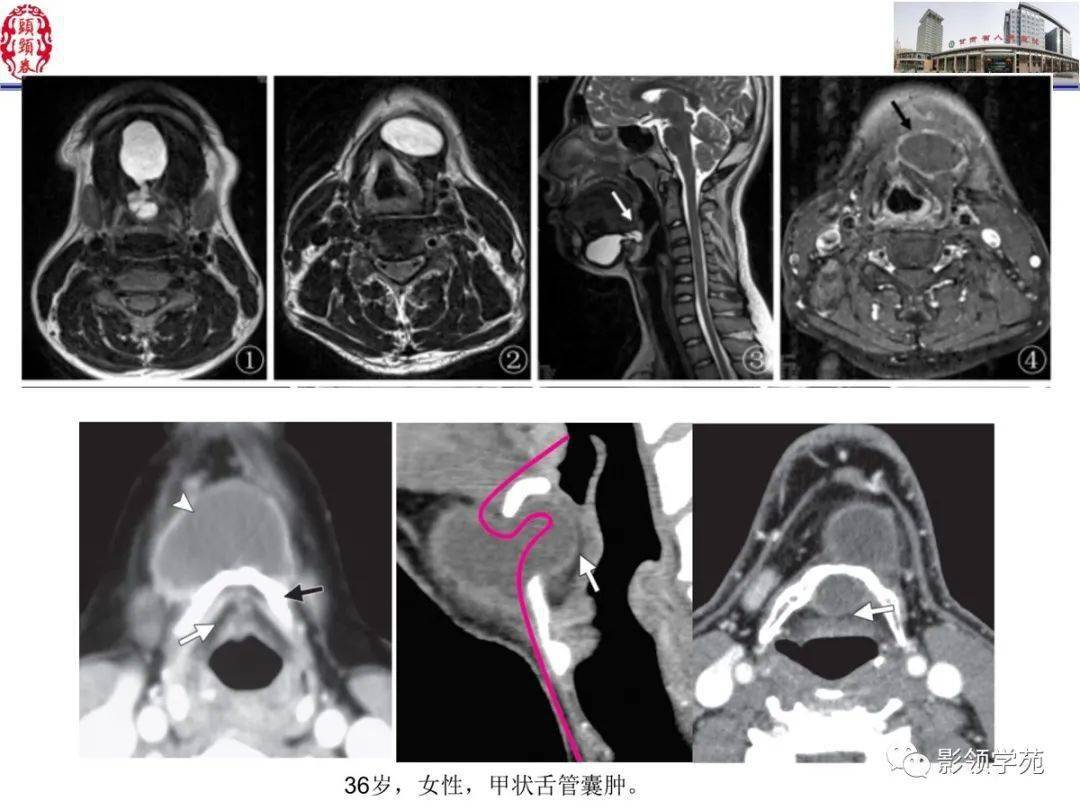

舌口底影像解剖及常见疾病影像诊断

舌,口底影像解剖及常见疾病诊断_平台